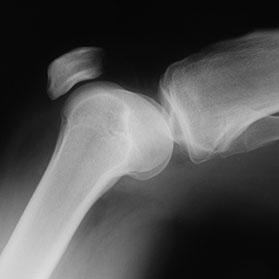

Saline fluid is first pumped into your knee to stretch it. Next, a narrow tube, with a small camera is inserted into one incision, so your surgeon can view the inside of your knee from a large monitor, while inserting surgical tools into the other hole, and correcting the problem.

Arthroscopic knee surgery is most commonly used to treat either a torn meniscus or chondromalacia [torn cartilage].

“The meniscus tear probably is the most common indication, and the reason it’s indicated is because in many people, the meniscus tears in an area that does not have good blood supply, and they don’t heal, so they continue to be symptomatic,” Dr. Thomas explains.